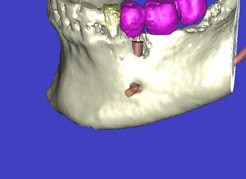

(siehe Bild 3 und 4).

Mit diesen gewonnenen Informationen und Planungen stellt der Zahnarzt interaktiv spezielle Bohrschablonen her. Diese ermöglichen eine exakte Positionierung der Implantate, so wie vorher am Computer geplant.

Weiterhin ist eine auf diese Weise geplante Operation für den Patienten weit weniger belastend. Denn die Freilegung des Knochens ist auf ein Minimum reduziert.